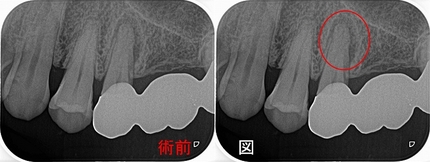

ブリッジの入っている歯を取り囲むように根尖病変があり、

レントゲン所見的に折れているかも!?

根尖と横の2本にガッタパーチャーが入り、

もしかしてこの2つの根尖病変が繋がり折れているようなレントゲン透過像になったのでは!?と疑う